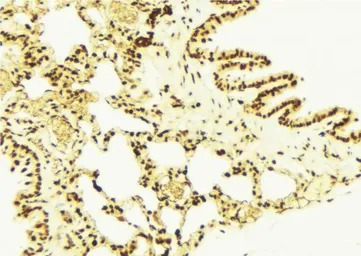

IHC-P analysis of mouse lung tissue using GTX02873 NRF2 (phospho Ser40) antibody.

Antigen retrieval : Heat mediated antigen retrieval step in citrate buffer was performed

Dilution : 1:100